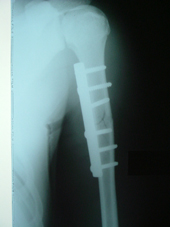

| Fracture Humerus |

Fracture humerus post op |

The Trauma Care Surgeons care for patients with recent or acute injuries as well as those who have chronic problems or complications of previous injuries such as delayed union and non union of fractures. Treatments are highly individualized and often include operative procedures as well as non-operative care such as splinting, bracing, and casting. Modern methods of surgery such as AO Fixation of Fractures , Interlocking Nailing of Fractures of Femur, Tibia and Humerus , LRS External fixation etc are routinely done . Rehabilitation after injury is a critical part of the treatment plan. Restoration of function, return to normal activities, and prevention of pain and deformity are our goals as we care for the total patient in a multidisciplinary environment.